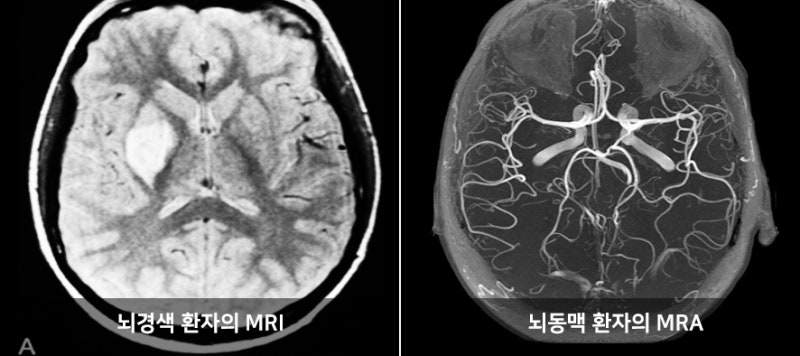

반면에 MRA는 혈관의 구조와 혈류를 시각화하는 데 집중된 기술입니다. 성공적인 심혈관 진단을 위해 혈관의 상태를 정확히 파악하는 것이 중요한데, MRA는 이러한 혈관 최적화 진단에 매우 효과적입니다. MRA는 MRI의 원리를 기반으로 하면서도, 특정한 혈관을 강조하여 더 잘 보기 위해 조영제를 사용하기도 합니다. 이로 인해, 의사는 혈관의 톤과 흐름을 보다 명확하게 관찰할 수 있으며, 협착증, 혈전, 기타 혈관 질병의 발견에 큰 도움을 줍니다. MRA와 MRI는 모두 안전한 검사 방법으로, 특히 방사선 노출이 없다는 점에서 의료진과 환자 모두에게 선호됩니다. 하지만 두 기술의 적용 분야와 사용하는 기법이 다르기 때문에 의사와 환자 모두가 각 기법의 특성을 잘 이해하고 활용하는 것이 중요합니다.

- 뇌혈관 질환 평가: 뇌졸중을 진단하기 위한 주요 진단 방식으로 활용되며, 뇌혈관의 이상을 조기에 발견할 수 있습니다.

MRA와 MRI는 각각 다른 목적과 용도로 사용되지만, 그 사용 분야나 필요한 경우에 따라 서로 보완적인 관계를 형성합니다. 이 두 가지 기술의 비교를 통해 각 기술이 사용하는 상황과 어떤 경우 통합적으로 적용될 수 있는지를 살펴보겠습니다. 특히 심혈관계 질환이나 다른 신체 부위의 질환이 동반되는 경우, 두 기술을 함께 사용한 복합적인 진단이 필요할 수 있습니다. 예를 들어, 심장질환 환자의 경우 MRI는 심장 및 주변 구조를 세부적으로 평가하는 데 활용될 수 있으며, 동시에 MRA를 통해 혈관의 상태를 평가함으로써 보다 전방위적인 접근이 가능합니다.